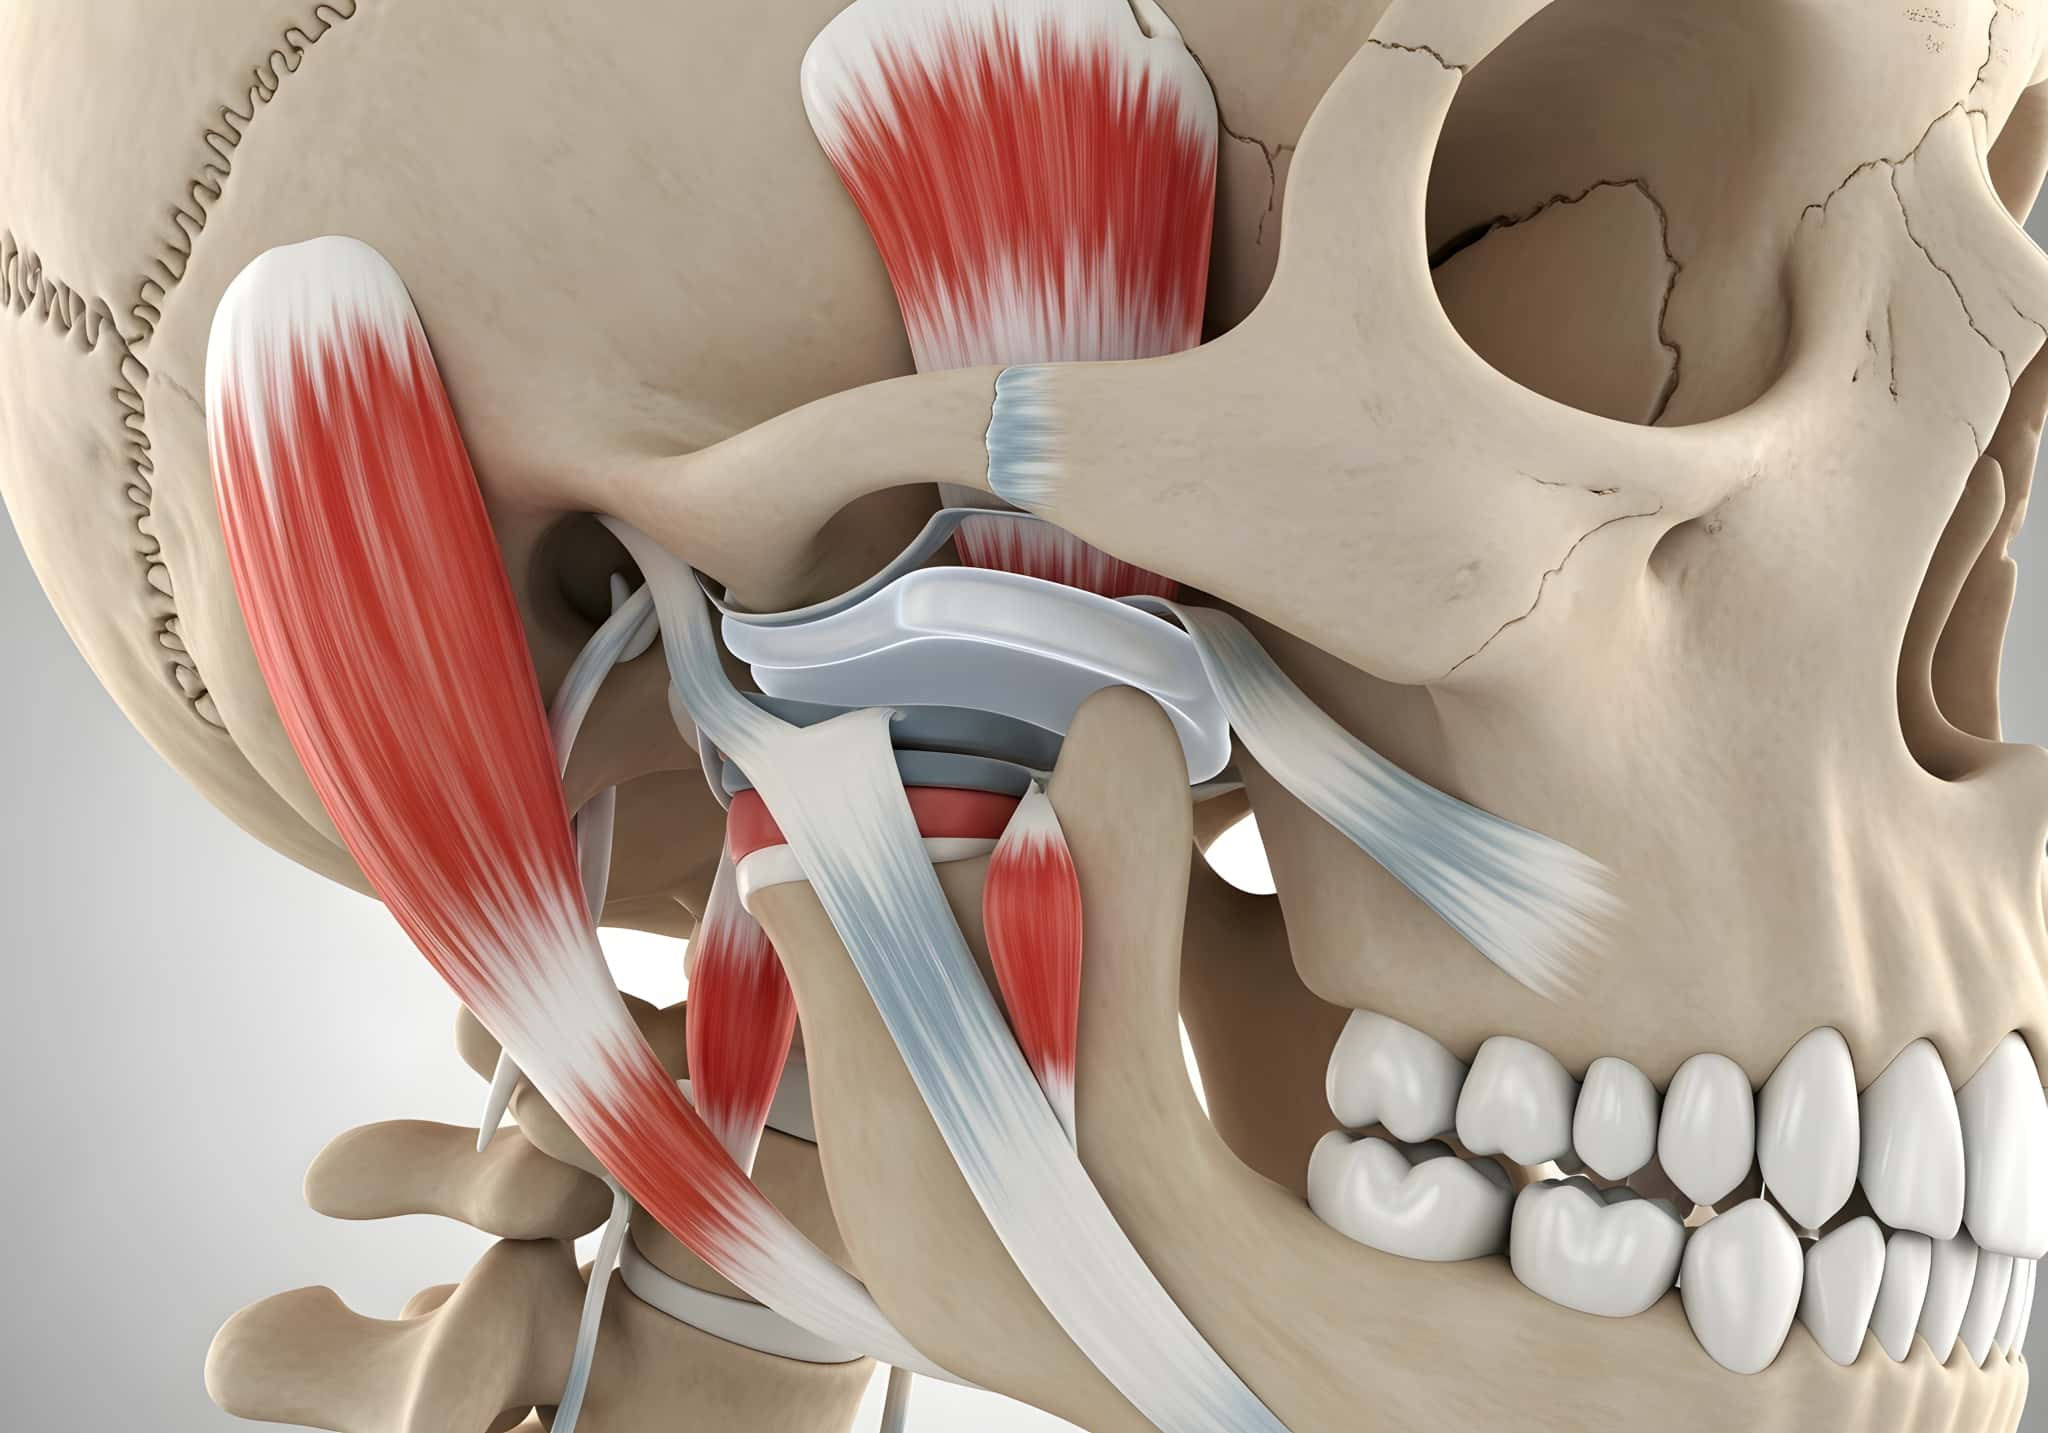

顎関節症とは

顎関節症は、顎の関節やその周囲の筋肉に異常が生じることで、痛みや違和感、開口障害などが現れる状態を指します。口を開けると音が鳴る、顎がだるい、スムーズに動かないといった症状が代表的です。

顎関節は、耳の前あたりに位置し、食事や会話など日常の動作に欠かせない重要な役割を担っています。この関節は非常に繊細で、わずかなバランスの乱れでも不調が生じやすい特徴があります。